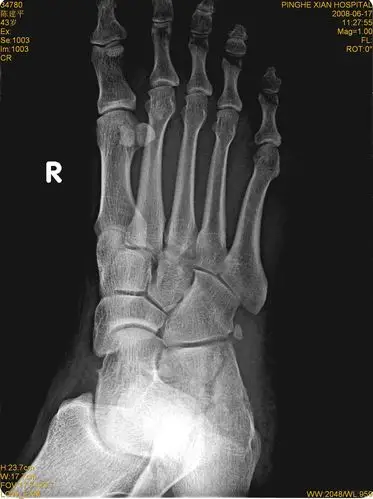

右足跟骨骨折 - 医学影像学讨论版 - 爱爱医医学论坛 - 爱爱医医学网